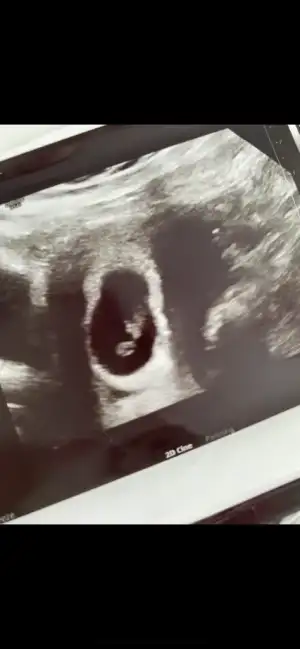

Sanırım bu teori en merak ettiğim teoriBence bebeğin konumu değişebiliyor o yüzden parlak alana odaklanmalıyız. Seninkinde bebek sağdaydı ama parlak alan net olarak sağda mıydı bi bakar mısın :) Kendimizi geliştirelim![]()